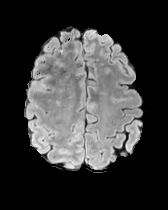

In Figures 2 and 4 we display examples of healthy images and anomaly maps obtained with the different approaches. We can observe that f-Ano GAN is not able to generate credible counterfactuals and generally produces images of poor quality and unrealistic appearance. On the other hand, the approaches based on diffusion models are able to create more high-quality results. However, the ones obtained with CG and CFG seem to present some artifacts, which may not only impact the realism of the counterfactual examples but also the precision of the anomaly maps obtained from them. In order to better quantify the capability of these methods to accurately segment pathological areas, we compute the Dice scores of the anomaly maps they generate.

We also test our approach on healthy samples. Ideally, we would like our generative process to act as the identity function when given a normal image as input. Some examples are shown in Figure 6, where we can observe that the changes introduced by our sampling technique are relatively minimal and Dif-fuse preserves the structure and general appearance of the images.